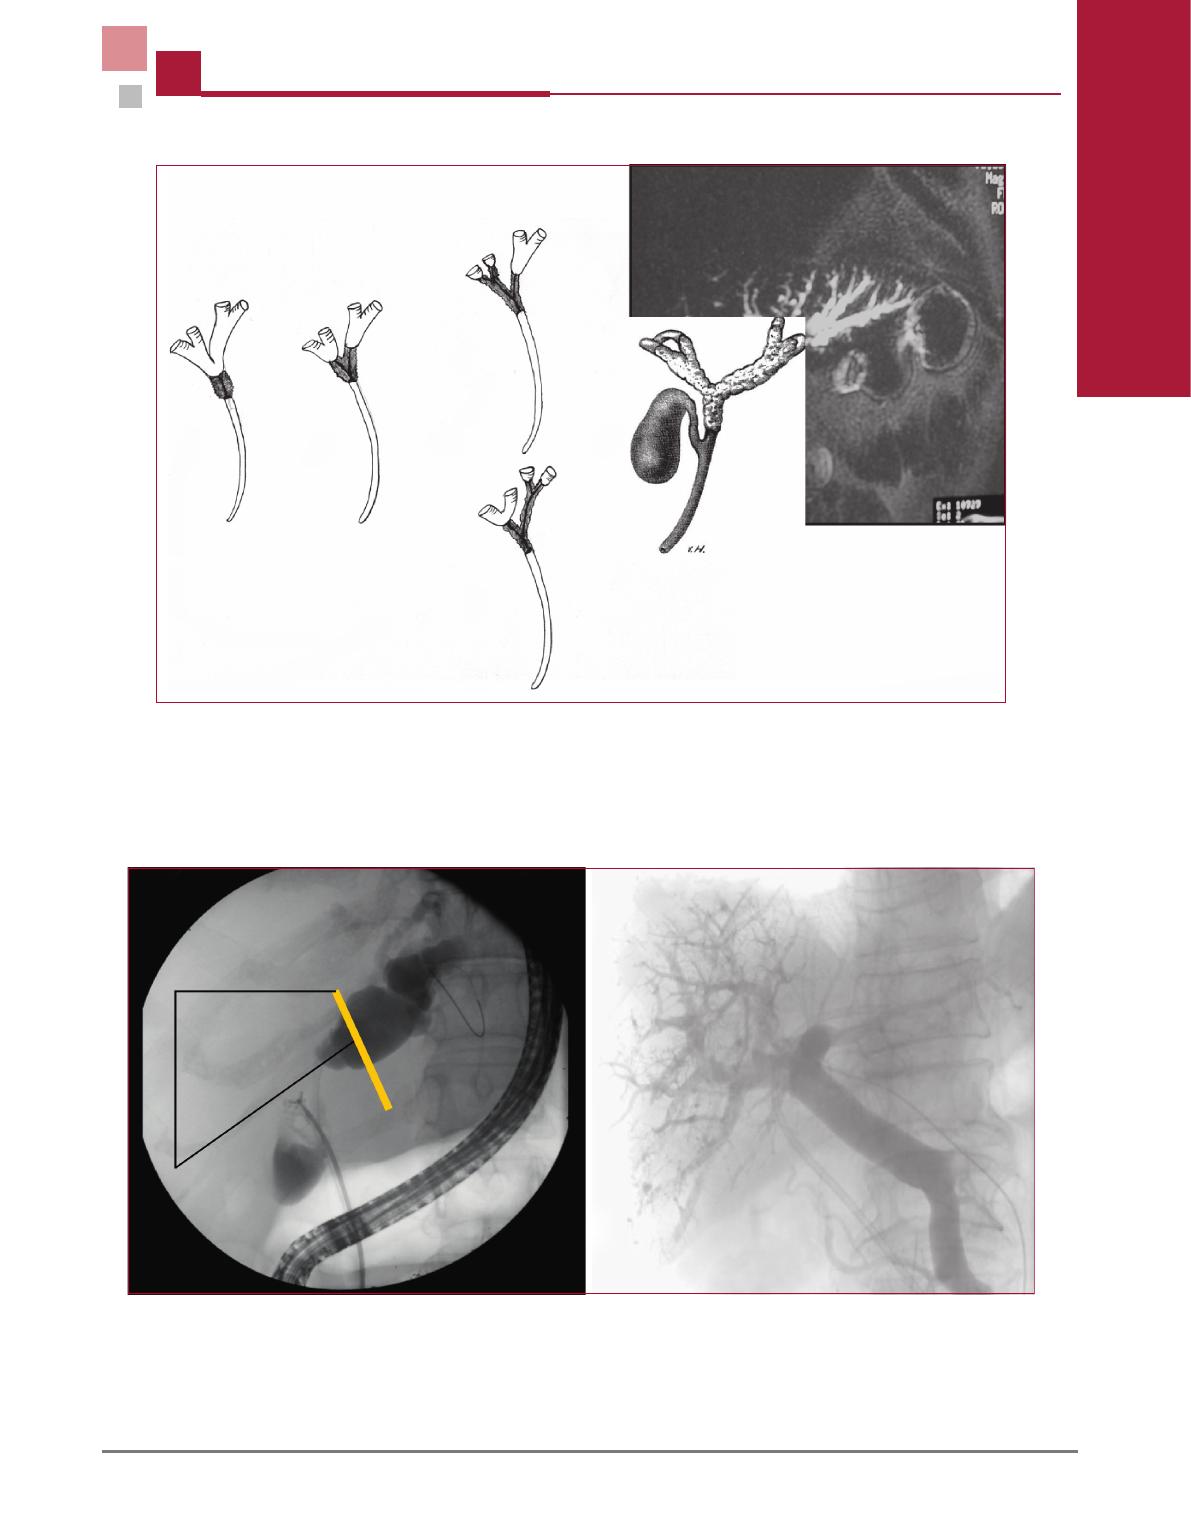

–techniques (h

epatectomie droite plus facile que gau-

che, reconstruction de la veine porte gauche plus facile,

r

esection du segment I plus facile apr

es h

epatectomie

droite que gauche, embolisation portale droite facile,

longueur anatomiquement plus grande du canal

h

epatique gauche) ;

–carcinologiques (branche de l’art

ere h

epatique

a

distance de la voie biliaire principale

a l’inverse de la

branche droite, plafond et plancher de la convergence

es

equ

es lors d’une h

epatectomie droite

etendue au

segment IV, principe de la r

esection carcinologique des

tumeurs du hile plus facile, longueur anatomiquement

plus grande du canal h

epatique gauche).